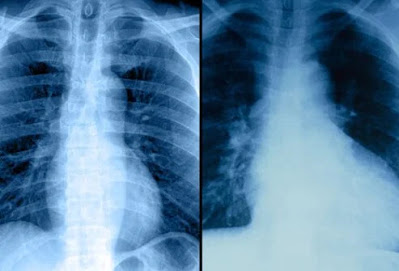

Έλεγχος καρδιακών παθήσεων: Ακτινογραφία θώρακα

Μια ακτινογραφία θώρακος μπορεί να βοηθήσει στον προσδιορισμό εάν κάποιος έχει διογκωμένη καρδιά ή συσσώρευση υγρού στους πνεύμονες λόγω καρδιακής ανεπάρκειας.

Οι ακτινογραφίες θώρακα μπορούν να παρέχουν περιορισμένες πληροφορίες σχετικά με την κατάσταση της καρδιάς. Οι ακτινογραφίες θώρακα χρησιμοποιούνται για να παρέχουν στον γιατρό μια εικόνα τόσο της καρδιάς όσο και των πνευμόνων για να καθοριστεί εάν υπάρχουν ανωμαλίες. Αυτές οι δύο ακτινογραφίες δείχνουν μια σχετικά φυσιολογική καρδιά στα αριστερά. Στη δεξιά ακτινογραφία, μια διογκωμένη καρδιά (κυρίως η αριστερή κοιλία) φαίνεται εύκολα και υποδηλώνει ότι ο κύριος θάλαμος άντλησης της καρδιάς δεν λειτουργεί κανονικά. Επιπλέον, οι ακτίνες Χ μπορεί να δείχνουν συσσώρευση υγρού στους πνεύμονες, πιθανώς από καρδιακή ανεπάρκεια.